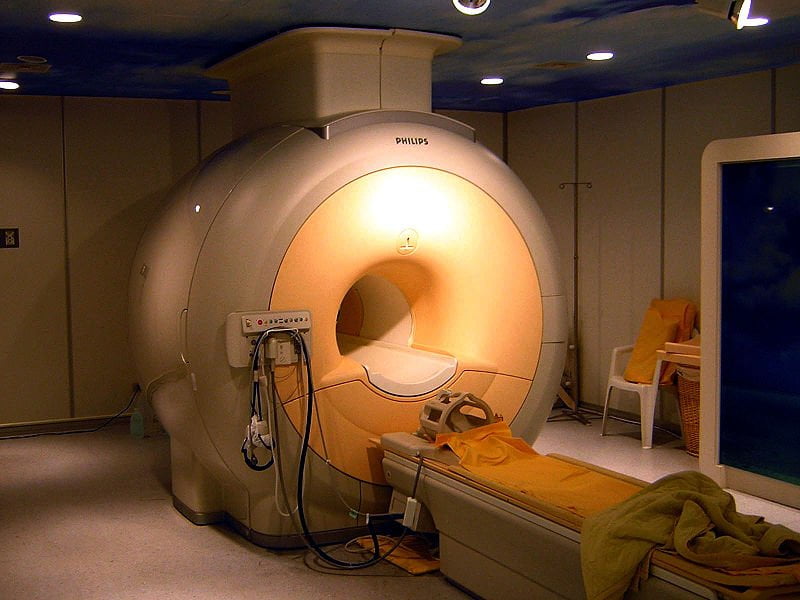

Este artículo es el tercero de la “mini-serie de las tomografías” dedicada a la Tomografía por Emisión de Positrones (TEP), [Tomografía Axial Computarizada (TAC)](https://eltamiz.com/2008/01/22/¿en-que-consiste-una-tomografia-axial-computarizada-tac/ “”), la Resonancia Magnética Nuclear (RMN), Imagen por Resonancia Magnética Nuclear (IRMN) o Tomografía por Resonancia Magnética (TRM) y, en un mes o dos, la ecografía. Como hicimos en los otros dos casos, hablaremos sobre los fundamentos físicos en los que se basa, cómo funciona técnicamente, para qué sirve y qué peligros entraña. Ojito a la secuencia de “rodajas” de una cabeza humana, que es algo grimosa pero fascinante. Yo juraría que es de Homer Simpson:

¿Sabes por qué la RMN hace ese ruido endiablado cuando funciona? ¿Y que, si te han hecho una, probablemente has estado rodeado por helio líquido a -269 ºC? ¿Quieres ver vídeos que muestran la potencia de los imanes superconductores empleados en esta técnica? Pues entonces sigue leyendo.

En cualquier caso, la RMN aprovecha las propiedades de los núcleos atómicos al someterlos a un intenso campo magnético y luego bañarlos en ondas de radio. Para hacer esto, un aparato de RMN utiliza tres dispositivos diferentes: un imán potente y fijo, imanes secundarios variables y bobinas emisoras/receptoras de ondas de radio.

La mayor parte de los imanes de los aparatos de IRMN actuales están hechos de una aleación superconductora de niobio-titanio, que se enfría hasta tan sólo 4 K (-269 ºC) con helio líquido, ¡tan sólo cuatro grados sobre el cero absoluto!. De este modo es posible lograr campos magnéticos intensísimos con una gran estabilidad: hasta 3 Teslas (unas 100.000 veces más intenso que el campo magnético de la Tierra).

Este imán es la razón de varias de las precauciones necesarias para lidiar con estos aparatos. Por un lado, salvo en el caso de los solenoides de cobre (que, como digo, ya no se usan), no se puede simplemente apagar y encender alegremente el imán: los ferromagnéticos son permanentes, y los superconductores requieren calentarse por encima de una temperatura crítica para perder la imantación, lo cual cuesta tiempo y dinero (pero mucho dinero). De modo que, de una forma u otra, cuando estás cerca de una de estas máquinas estás en el seno del campo magnético más intenso que hayas experimentado jamás.

Las buenas noticias son que un campo magnético estático de esa intensidad no tiene efectos apreciables sobre nuestro organismo. Las malas noticias son que cualquier material ferromagnético sí se ve afectado, ¡y cómo! No te pierdas este vídeo en el que se muestra el comportamiento de un extintor metálico al acercarlo a una máquina de RMN:

Esto hace que se extremen las medidas de seguridad antes de acercarse a una de ellas: cualquier objeto metálico podría salir disparado hacia el centro del imán como el extintor y herir a la persona que estuviera dentro. Esto no quiere decir que siempre se sigan las normas de seguridad, lo cual produce a veces contratiempos incómodos, sobre todo porque, como he dicho, desconectar el imán muchas veces no es una opción:

Cuando se realiza una TRM, los electroimanes secundarios se encienden y se apagan muchas veces. Naturalmente, al ser imanes dentro de un campo magnético muy intenso, sufren fuerzas magnéticas variables durante el examen, lo cual hace que se “bamboleen” dentro de la máquina una y otra y otra vez. Esto produce un ruido que puede llegar a tener 130 dB (lo cual es realmente tremendo) y puede ser muy molesto; de hecho, requiere algún tipo de protección para los oídos, porque una RMN puede llegar a durar una hora y media. Nunca me he sometido a una, ¡pero vuestras experiencias son bienvenidas en los comentarios!

En la duración del proceso, además del reducido tamaño del túnel en el que te introducen, está otro problema de esta técnica: tienes que estar tumbado en un sitio agobiante, muy quieto (¡porque si no los protones se salen del sitio que les corresponde según su frecuencia de Larmor!), con un ruido infernal… mucha gente no lo puede soportar, sobre todo si sufre de claustrofobia, son ancianos o niños, etc. En algunos casos puede sedarse al paciente para que se tranquilice, o incluso anestesiarlo.